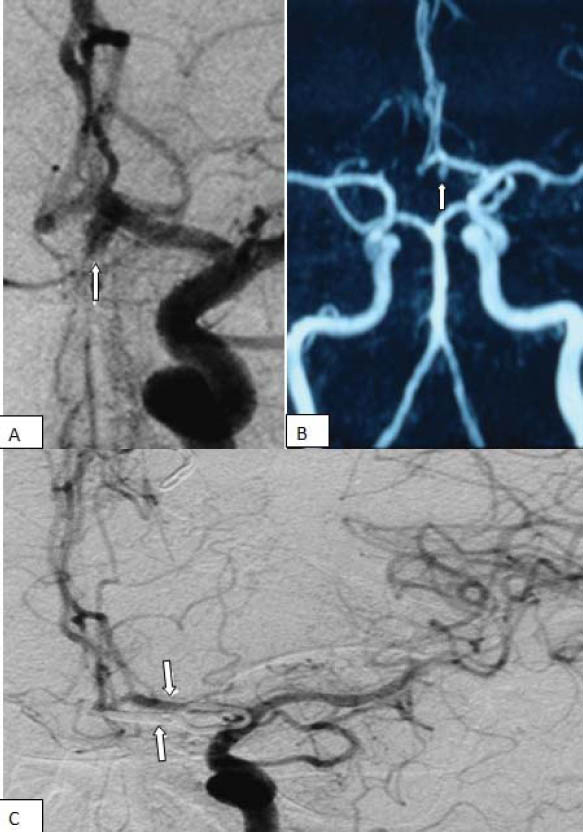

The aim of our study was to report a series of 15 consecutive patients with aneurysms of the proximal segment (A1) of the anterior cerebral artery. In 15 patients with diagnosed A1 aneurysms, representing 2.1% of 720 aneurysm patients treated at a University Clinical Center between October 1999 and August 2012, clinical presentation, neuroradiological findings, surgical treatment methods and outcome were retrospectively analyzed. Mean patient age was 53.06 (range 32 to 75) years. Ten saccular aneurysms were treated with micro neurosurgical approach via standard pterional craniotomy, four fusiform aneurysms with coiling, and one fusiform aneurysm with stent. No patients died during the operation. The mean follow-up period was 32 months (range 5 months to 7 years). Clinical outcomes revealed good recovery in all patients. Despite the general opinion that A1 aneurysms are benign lesions, an increasing number of reports have demonstrated their potential complications. To date, due to the rarity of A1 aneurysms, only a few consecutive series have been reported. Conduct of multicenter studies are required in order to understand clinical features of A1 aneurysms and devise a proper treatment plan.